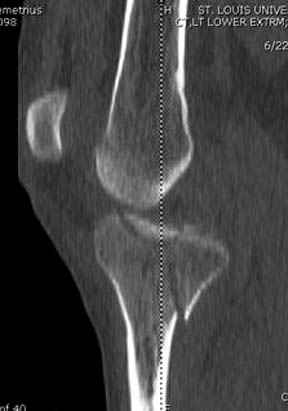

На представленных предоперационных срезах КТ огромный задне-медиальный фрагмент расположен больше кзади, чем медиально. Для планирования, кроме поперечных срезов, надо ориентироваться на корональные срезы, которые укажут топографию верхушки медиального фрагмента.